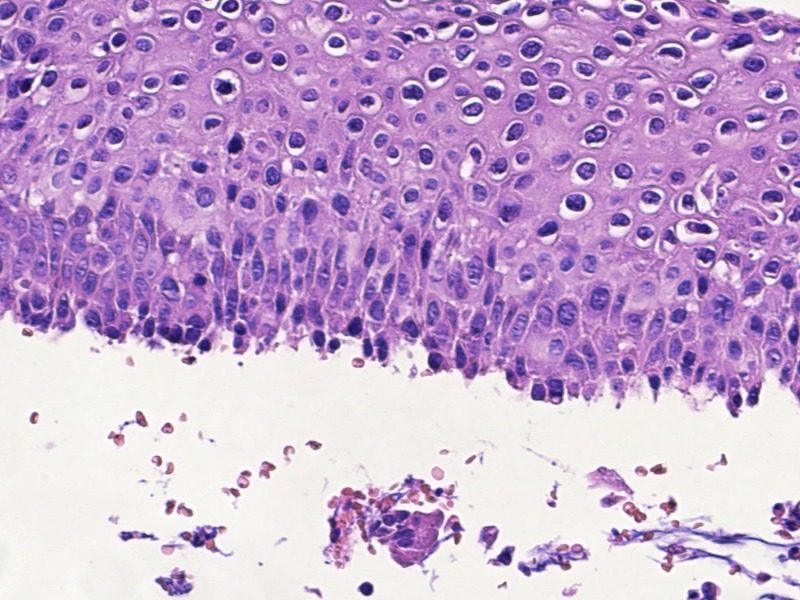

宫颈活检高级别?

TCT:ASC-US HPV:52+

宫颈活检

1、宫颈活检:灰白组织9块,直径0.3-0.5cm,质软,全取包。

图2

LSIL。

基底样细胞没有那么多,低级别够了